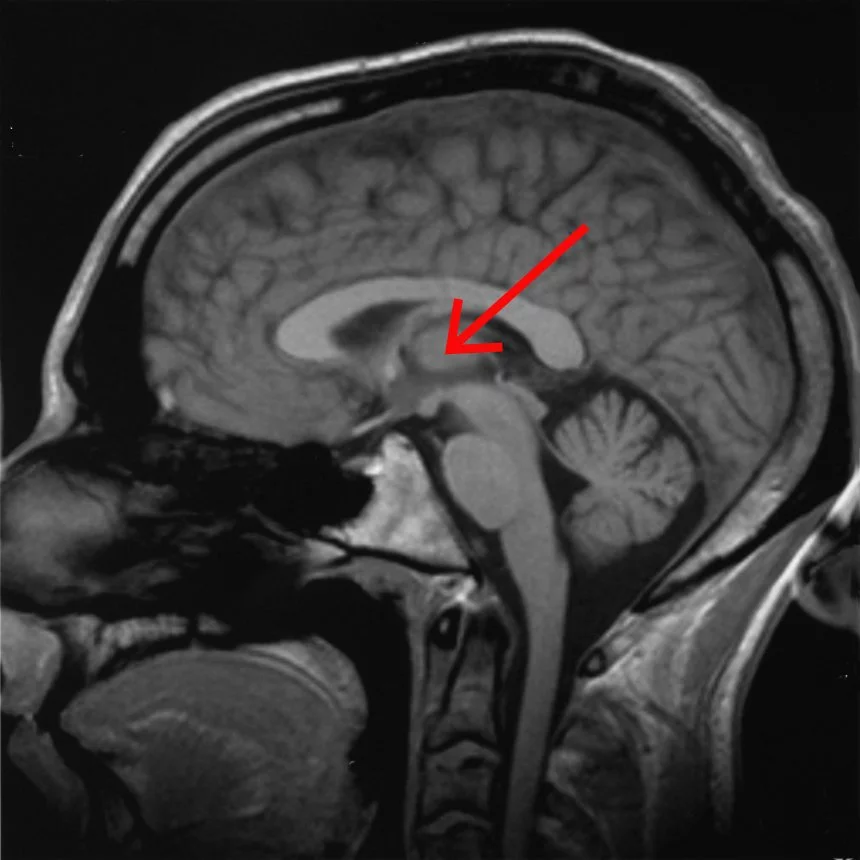

Scientists have long been studying the thalamus, which sits deep in the brain near the brain stem, to learn what role it plays in sleep, waking, consciousness and alertness. But this research, in which targeted electrical stimulation was applied to a specific area, narrowed the search down further than ever before. The electrodes used in the study were more tailored to the shape of the brain structures they were designed to work on, and the electrical stimulation was designed to mimic the activity of a normal, waking brain.